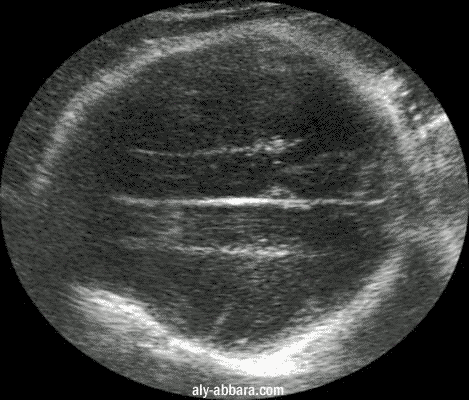

Coupe coronale au niveau du crâne fœtal à 30 SA mettant en évidence

la faux du cerveau et le bord supérieur des ventricules latéraux

La faux du cerveau est un repli courbe de la dure-mère qui sépare les deux hémisphères du cerveau.